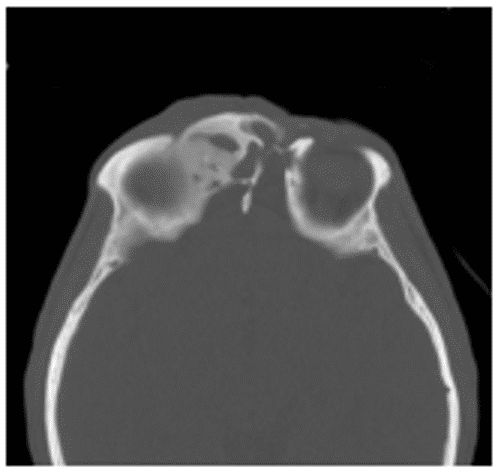

При фиброзной дисплазии верхней челюсти патологический процесс сравнительно быстро распространяется на верхнечелюстной синус, альвеолярный, скуловой и лобный отростки. При вовлечении в процесс медиальной стенки верхнечелюстной пазухи может наблюдаться сужение или облитерация носослезного канала, носовых ходов, деформация перегородки носа (рисунок 8).

Рис. 8. КТ околоносовых пазух, аксиальная проекция (А) и реконструкция в коронарной плоскости (Б). Фиброзная дисплазия обеих верхнечелюстных пазух с поражением скуловых отростков (остеоцементодисплазия)

Пораженная верхнечелюстная кость и скуловые отростки имеют неоднородную структуру, на фоне которой вокруг корней зубов определяются обширные высокоплотные зоны (цементикли).